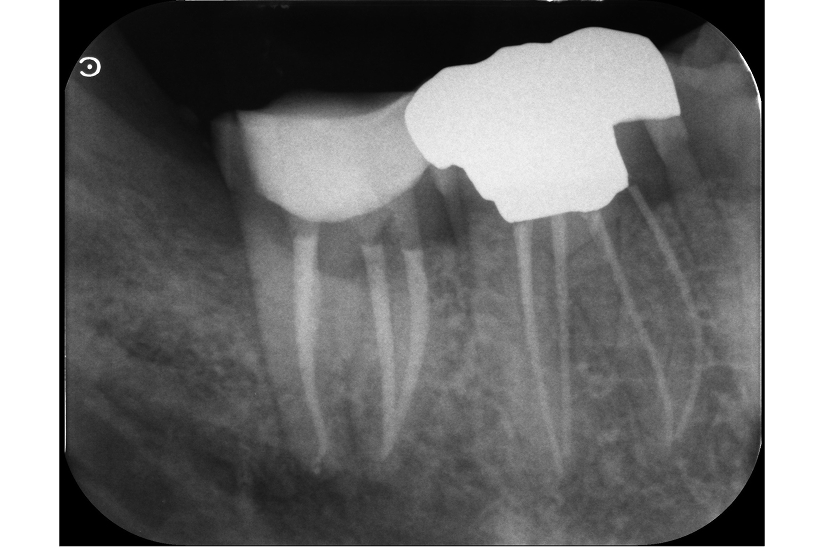

根尖性歯周炎の歯を

再根管治療によって歯を残した症例

タップで写真の拡大ができます。

Before

After

Under Treatment

主訴

抜歯が必要と言われた歯の精査を希望

診断

根尖性歯周炎(根尖吸収、ストリップパーフォレーションを伴う)

治療方針

重度の感染および根管内の損傷が認められる難症例であったが、 歯質の残存量および歯周組織の状態から保存可能と判断した。

歯根破折を疑う所見も認められなかったため、 患者の希望も踏まえ、保存的に再根管治療を行う方針とした。

治療内容

リトリートメント(大臼歯)、MTAセメントによる封鎖、レジンコア

治療期間

約1ヶ月

治療費用

220,000

結果

初診時には根管内に肉芽組織および排膿を認めたが、 感染コントロール後に炎症所見は消失した。

その後MTAセメントにて封鎖を行い、 術後症状は認めず、根尖病変は縮小傾向を示している。

治療の

リスク

根尖病変が完全に消失しない可能性

考察

複数回の根管治療既往があり、根管内は複雑な状態であったが、 適切な感染源の除去と封鎖により良好な経過が得られている。

難症例においては、保存の可否を適切に判断した上で、 精密な処置を行うことが重要である。